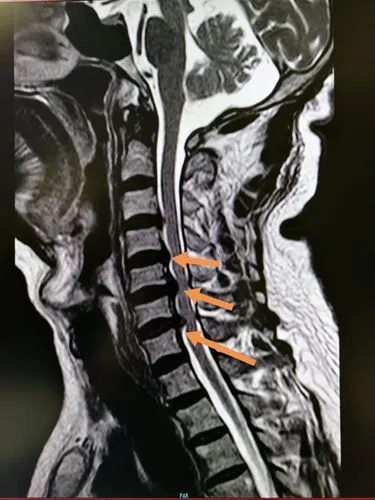

- 颈椎间盘突出

和腰椎间盘突出类似,可能是因为跳跃或者长时间低头导致

![]()